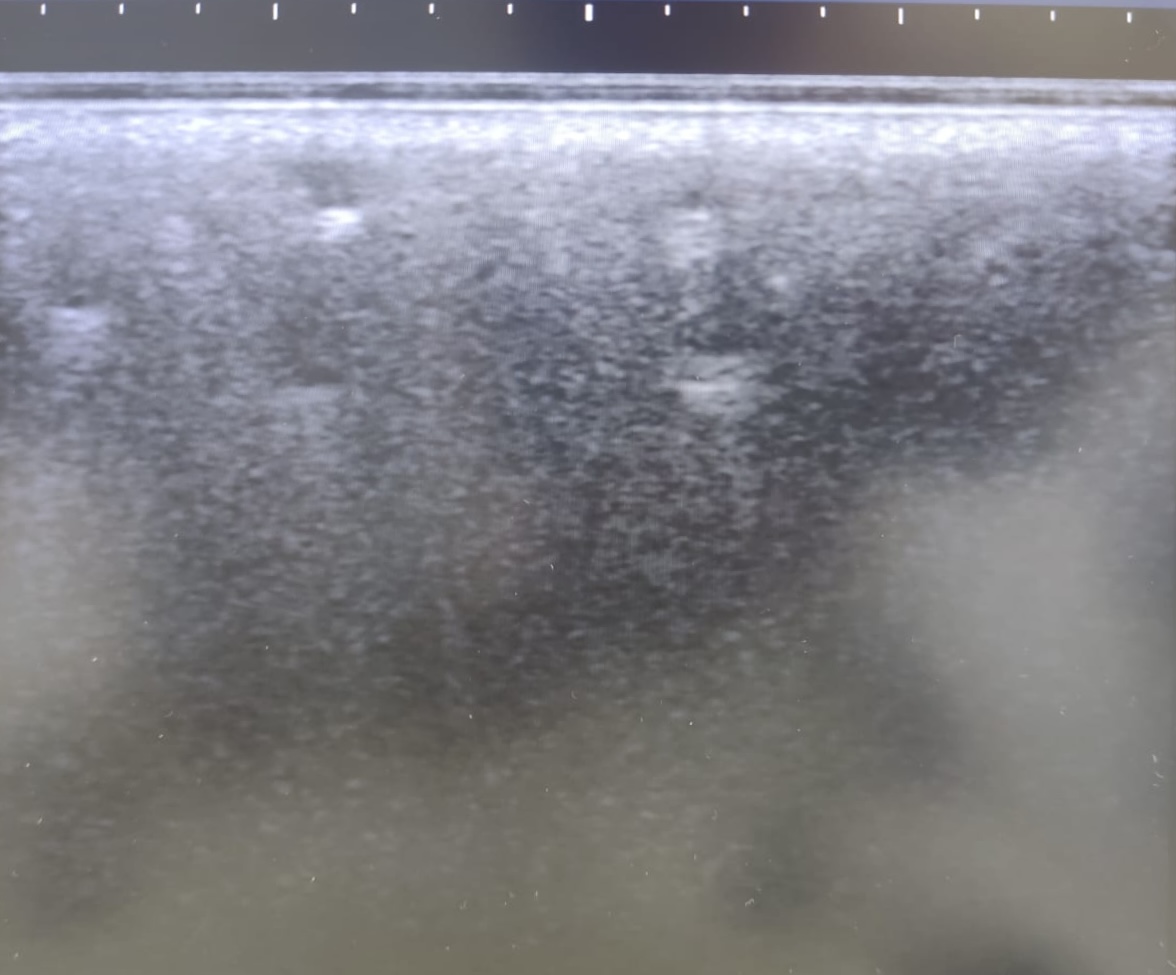

Ecografía clínica: se realiza ecografía clínica de partes blandas en consulta con evidencia de múltiples lesiones hipoecoicas y anecoicas bien definidas, con bordes regulares y sombra posterior compatibles con silicona líquida migrada en zona postero-interna de extremidad inferior derecha.